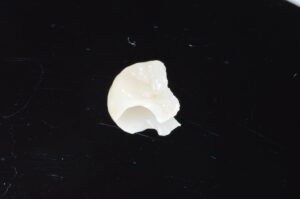

e.max(イーマックス)

ドイツのイボクラーという会社が開発したセラミックです。透明感があり綺麗ですが、美しさは陶材には劣ります。しかし、天然の歯と同じくらいの硬さで、陶材よりも強度が高く、奥歯にも使用できるので、使い勝手が良い優れた材料です。→イボクラーのHPhttps://www.ivoclar.com/ja_jp

e.max(イーマックス)クラウン or インレー

e.maxのみで作られた被せ物(クラウン)やインレー(詰め物)です。プレスタイプとミリングタイプ(削り出し)があり、プレスタイプの方が技工士さんの手作業が多くなる分、精度が高くなります。ミリングタイプはマシンがe.maxのブロックを削って作成するので、精度はやや落ちますが、強度面は安定しています。インレーを作る場合は現在最も審美的な材料です。